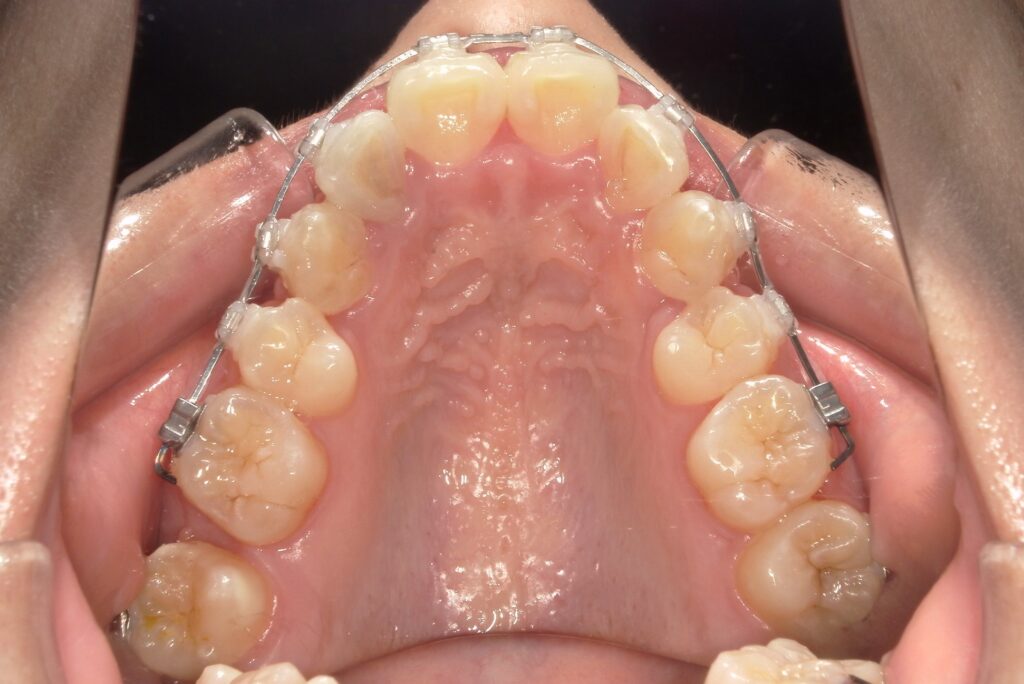

【治療経過】八重歯矯正を始めて1か月後の歯並び変化

治療を開始してから約1か月が経過しました。

上顎の第一小臼歯を抜歯し、ワイヤー矯正をスタートさせています。写真でもお分かりいただけるように、抜歯したスペースを利用して歯を動かす準備が整いつつあります。

この時期は、見た目の大きな変化はまだ少ないものの、歯がじわじわと動き始め、歯列が並ぶための基盤が作られていく大切な段階です。